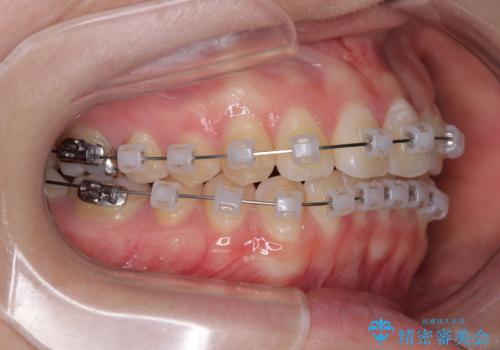

治療方法としては、装置の目立ちにくさと費用面のバランスを考慮して、プラスチック製のクリアブラケットとメタルワイヤーを組み合わせた矯正装置を使用することにしました。